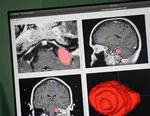

We are working to develop new technologies that combine a new type of camera system, referred to as hyperspectral, with Artificial Intelligence (AI) systems to reveal to neurosurgeons information that is otherwise not visible to the naked eye during surgery. Two studies are currently bringing this “hyperspectral” technology to operating theatres. The NeuroHSI study uses a hyperspectral camera attached to an external scope to show surgeons critical information on tissue blood flow and distinguishes vulnerable structures which need to be protected. The NeuroPPEye study is developing this technology adapted for surgical microscopes, to guide tumour surgery.